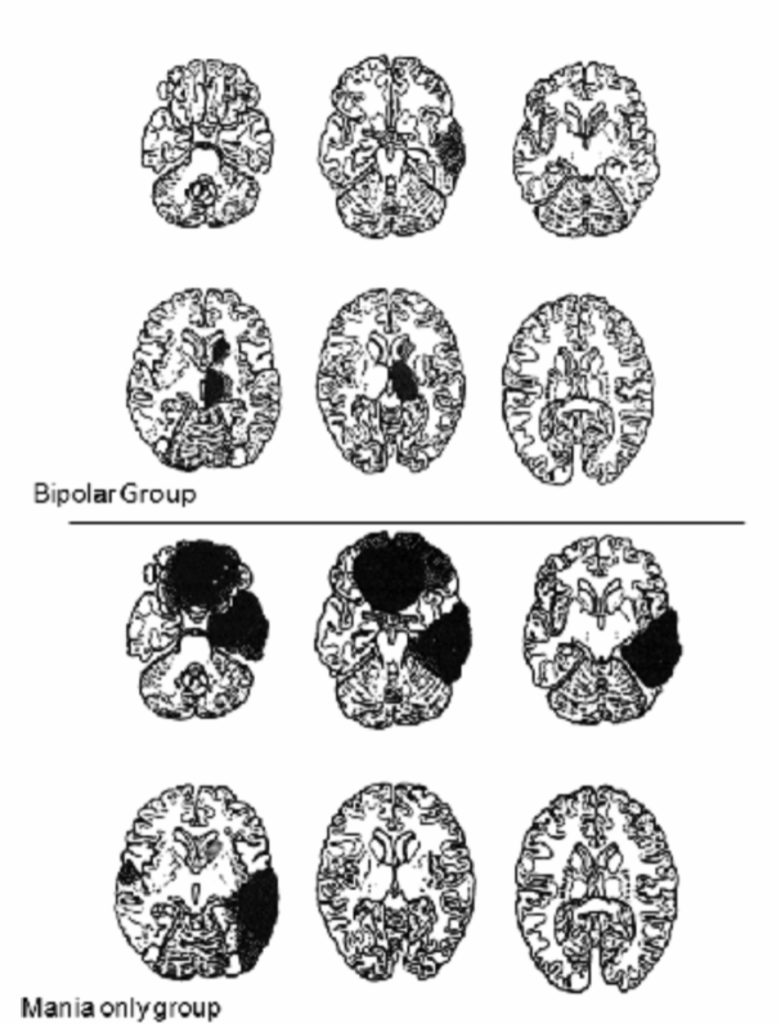

脳卒中後の躁病の経過は、系統的に調べられていません。躁病または抑うつの再発エピソードがこれらの患者に起こる可能性があることを示す症例報告がされています(図2.2-5)。

図2.2-5. 双極性障害または躁病のみの患者における脳卒中病変の脳画像

この図は、双極性障害または躁病のみの患者における脳卒中病変の脳画像を示しています。

- 双極性群(Bipolar Group): 躁うつ病患者の病変の最大断面を示すCTスキャン画像テンプレート。病変は主に右尾状核頭部と右視床に認められました。

- 躁病のみの群(Mania only group): 躁病のみの患者の病変の最大断面を示すCTスキャン画像テンプレート。病変は主に眼窩前頭皮質と右側頭底皮質に認められました。

(Robinson RG. The Clinical Neuropsychiatry of Stroke: Cognitive, Behavioral and Emotional Disorders following Vascular Brain Injury. 2nd ed. Cambridge University Press; 2006:302より許可を得て転載。)